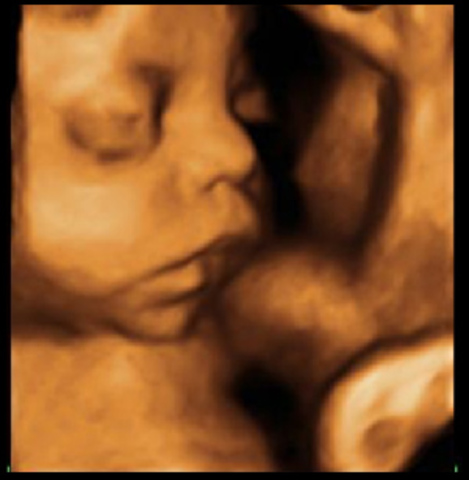

Los ojos del bebé se comienzan a abrir y cerrar regularmente pero aun cuando el color ya está genéticamente determinado este solo se podrá conocer después de los 6-8 meses de nacido. Su bebé alterna ciclos de sueño/vigilia cada 20 a 30 minutos. Los movimientos fetales se hacen muy obvios cuando usted se relaja, sentada o acostada, especialmente durante la noche. Los rasgos faciales son muy claros